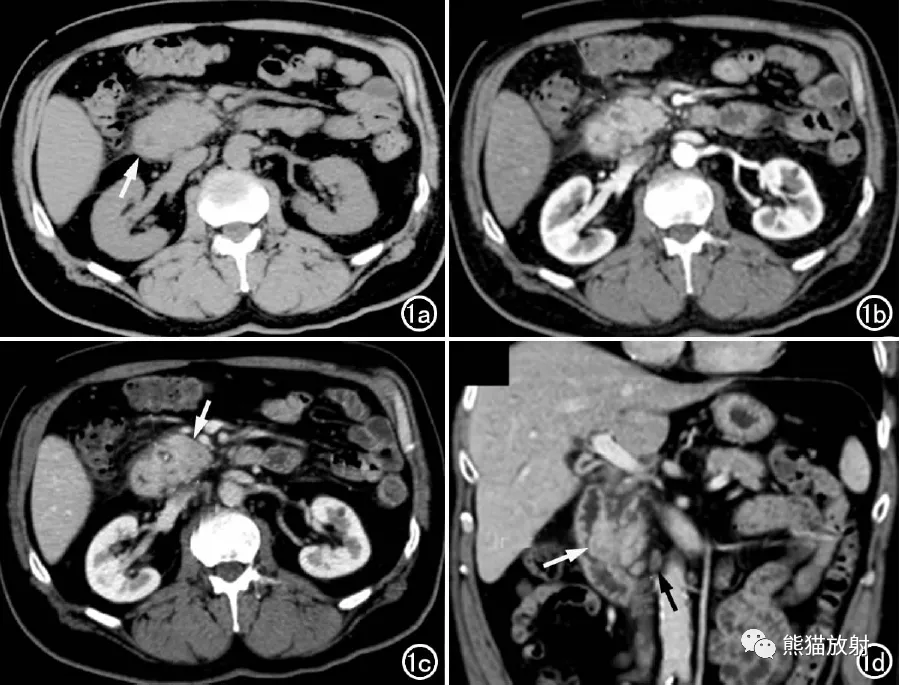

图2 男 , 66岁 , 弥漫型GP 。 CT增强扫描实质期示十二指肠降部管壁环形增厚(长箭) , 胃十二指肠动脉受推移(短箭) 。

图3 男 , 73岁 , 节段型GP 。 CT增强扫描实质期示胰头部囊性病灶(长箭) , 伴有沟槽区积液(短箭) , 胆囊炎、胆囊呈香蕉状形态(*) 。